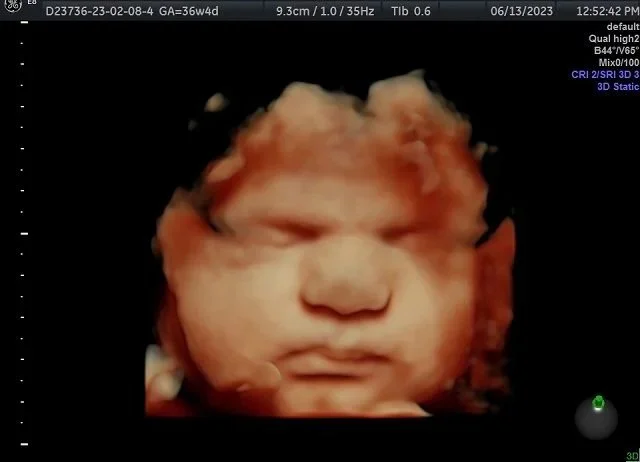

60-minute 3D/4D/HD Ultrasound

Looks best at 28 weeks+ but can be done as early as 15 weeks

This full hour appointment is great for bringing guest! We will see baby’s face, hands and feet, check for a head of hair!

8 Ultrasound sound prints

4. 4x6 colored prints

Baby’s estimated Weight

Baby Position

Hear Heartbeat

$158

Come again and again for $90

To book this use the “returning visit” tab upon booking.

The Finale

35-40 WEEKS ONLY

15-minute 2D ultrasound

Add on a 3D image if position allows for $15. The tech will ask you before your appointment starts if you are wanting these images and if agreed upon, they will attempt if baby is in a good spot. Not all will be.

6 Ultrasound prints

Starting price $53 with the 3D add on $68